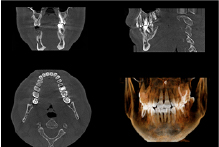

安全かつ確実な治療の土台を築くため、歯科用CT、レントゲン、口腔内写真撮影など、各種精密検査を実施します。高性能な設備を用いてお口や顎の骨の状態、そして全身の健康状態まで正確に把握し、インプラント治療の適性を判断いたします。

サージカルガイドは、インプラント手術の正確性を飛躍的に高めるために開発された、カスタムメイドのマウスピース状の器具です。

事前のCT検査やシミュレーションで導き出された「インプラント埋入の最適な位置、角度、深さ」を、このガイドが手術中に正確にアシストします。

これにより、血管や神経などの重要な組織を傷つけるリスクを最小限に抑え、シミュレーション通りの安全で低侵襲な手術を実現します。術後のトラブル防止にも大きく貢献し、患者様により安心できるインプラント治療を提供します。